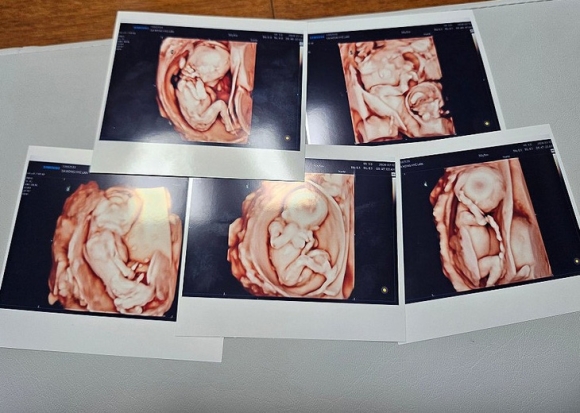

Ảnh siêu âm của năm em bé trong ca sinh năm được thụ thai tự nhiên đầu tiên tại Hàn Quốc - Ảnh: YONHAP

Hôm 20-9, vợ chồng anh chị chào đón năm em bé, gồm ba bé trai và hai bé gái tại Bệnh viện Saint Mary Seoul, thủ đô Seoul.

Đây cũng chính là ca sinh năm được thụ tinh bằng phương pháp mang thai tự nhiên đầu tiên tại Hàn Quốc.